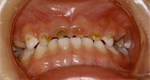

|

治療前 |